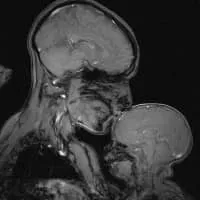

Rebecca Saxe photograph

Rebecca Saxe Photos